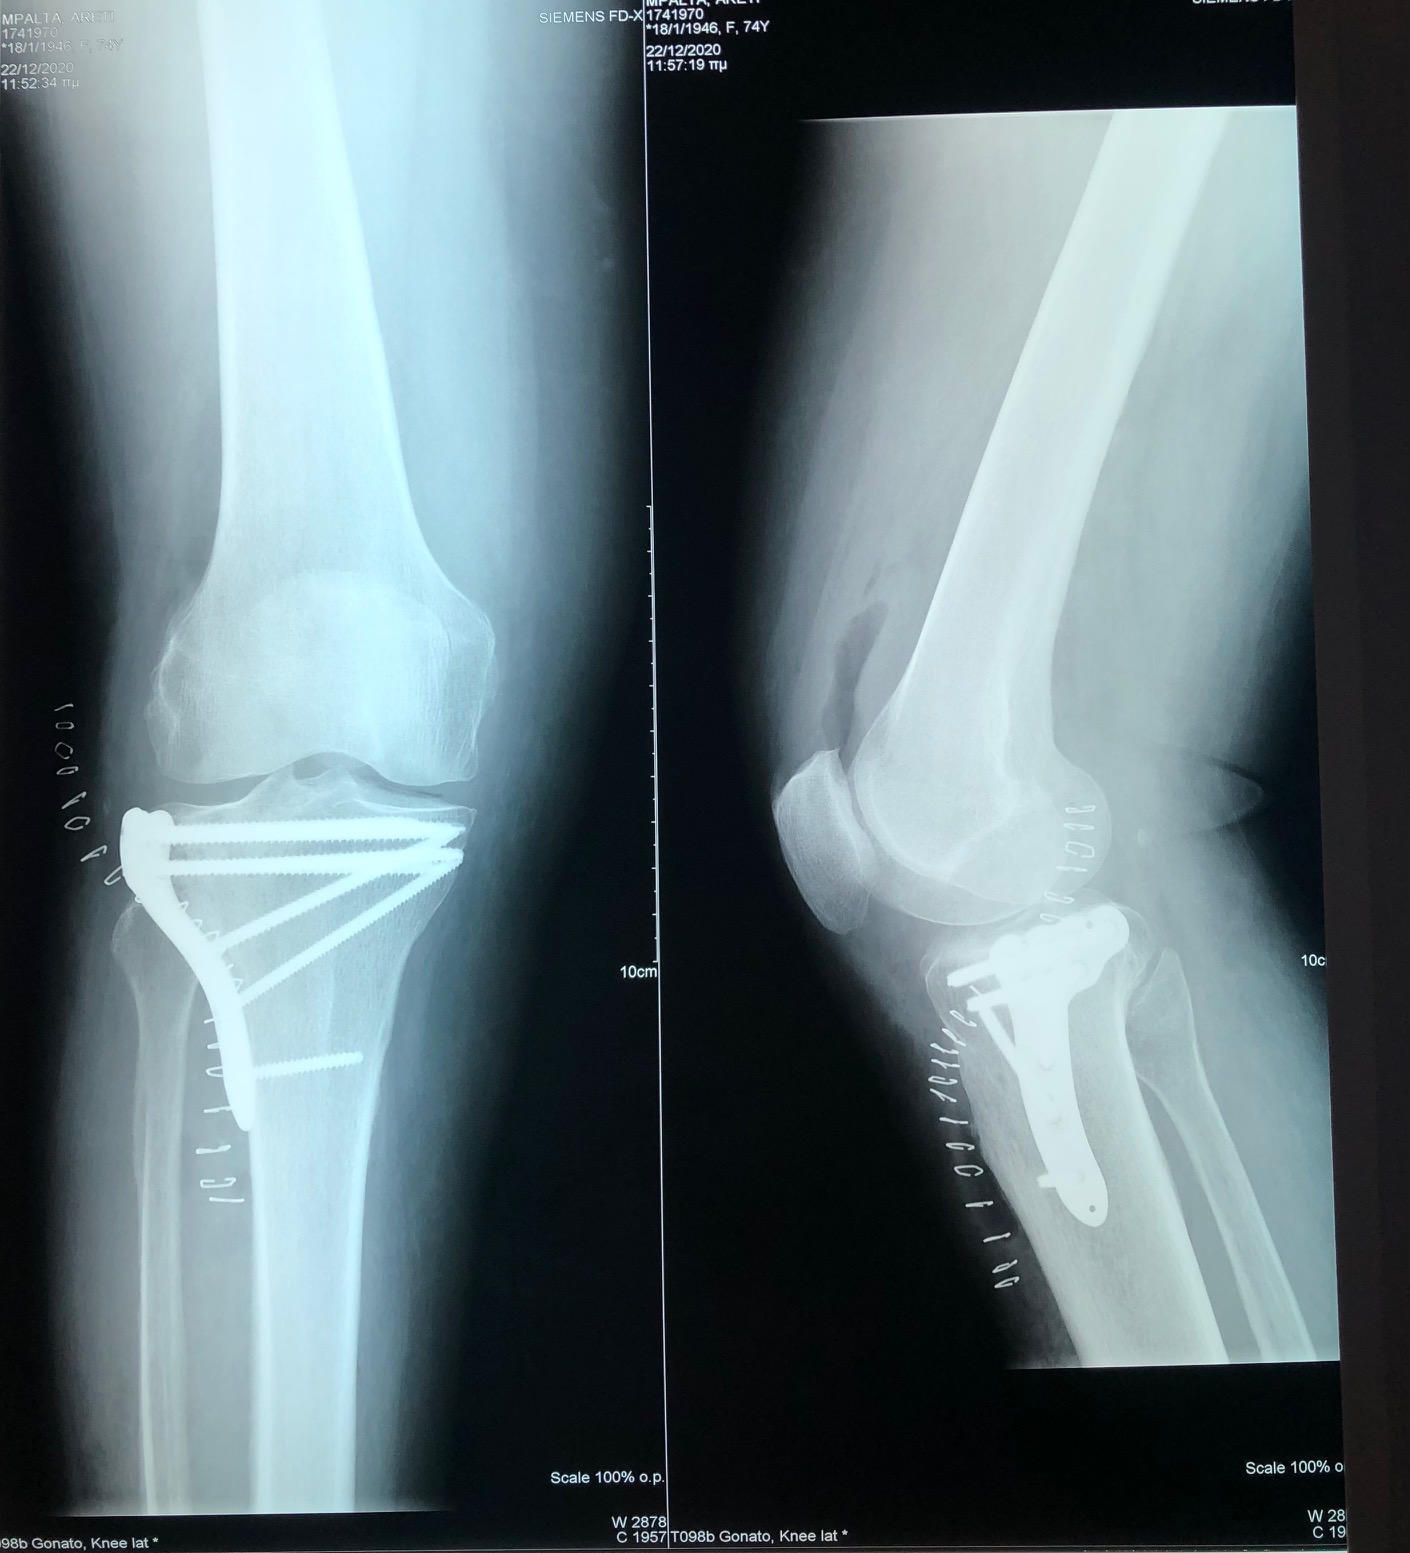

Η διάγνωση ενός κατάγματος κνημιαίου plateau πραγματοποιείται από έναν έμπειρο Ορθοπαιδικό. Αρχικά η λήψη ενός λεπτομερούς ιστορικού και η κλινική εξέταση του ασθενούς είναι απαραίτητα. Στην συνέχεια για την διάγνωση αλλά και την ταξινόμηση του κατάγματος είναι υποχρεωτική η διενέργεια ακτινολογικού ελέγχου. Ο έλεγχος αυτός περιλαμβάνει απλές ακτινογραφίες (φας, προφιλ και λοξές) ενώ πολλές φορές απαιτείται περαιτέρω διερεύνηση με αξονική τομογραφία για την πλήρη κατανόηση της μορφής του κατάγματος και τον σωστό προεγχειρητικό σχεδιασμό.

Σε κατάγματα του κνημιαίου plateau με μεγάλη συντριβή, με εμβύθιση της αρθρικής επιφανειας ή σε ασθενείς με αθλητική δραστηριότητα συστήνεται η χειρουργική αντιμετώπιση. Αυτή συνίσταται στην ανοικτή ανάταξη του κατάγματος και την εσωτερική οστεοσύνθεση του (τοποθέτηση πλάκας και βιδών), την τοποθέτηση εξωτερικής οστεοσύνθεσης ή στον συνδυασμό μεθόδων. Σε επιλεγμένα περιστατικά μπορεί να γίνει η ανάταξη του κατάγματος υπό αθροσκοπικό έλεγχο.